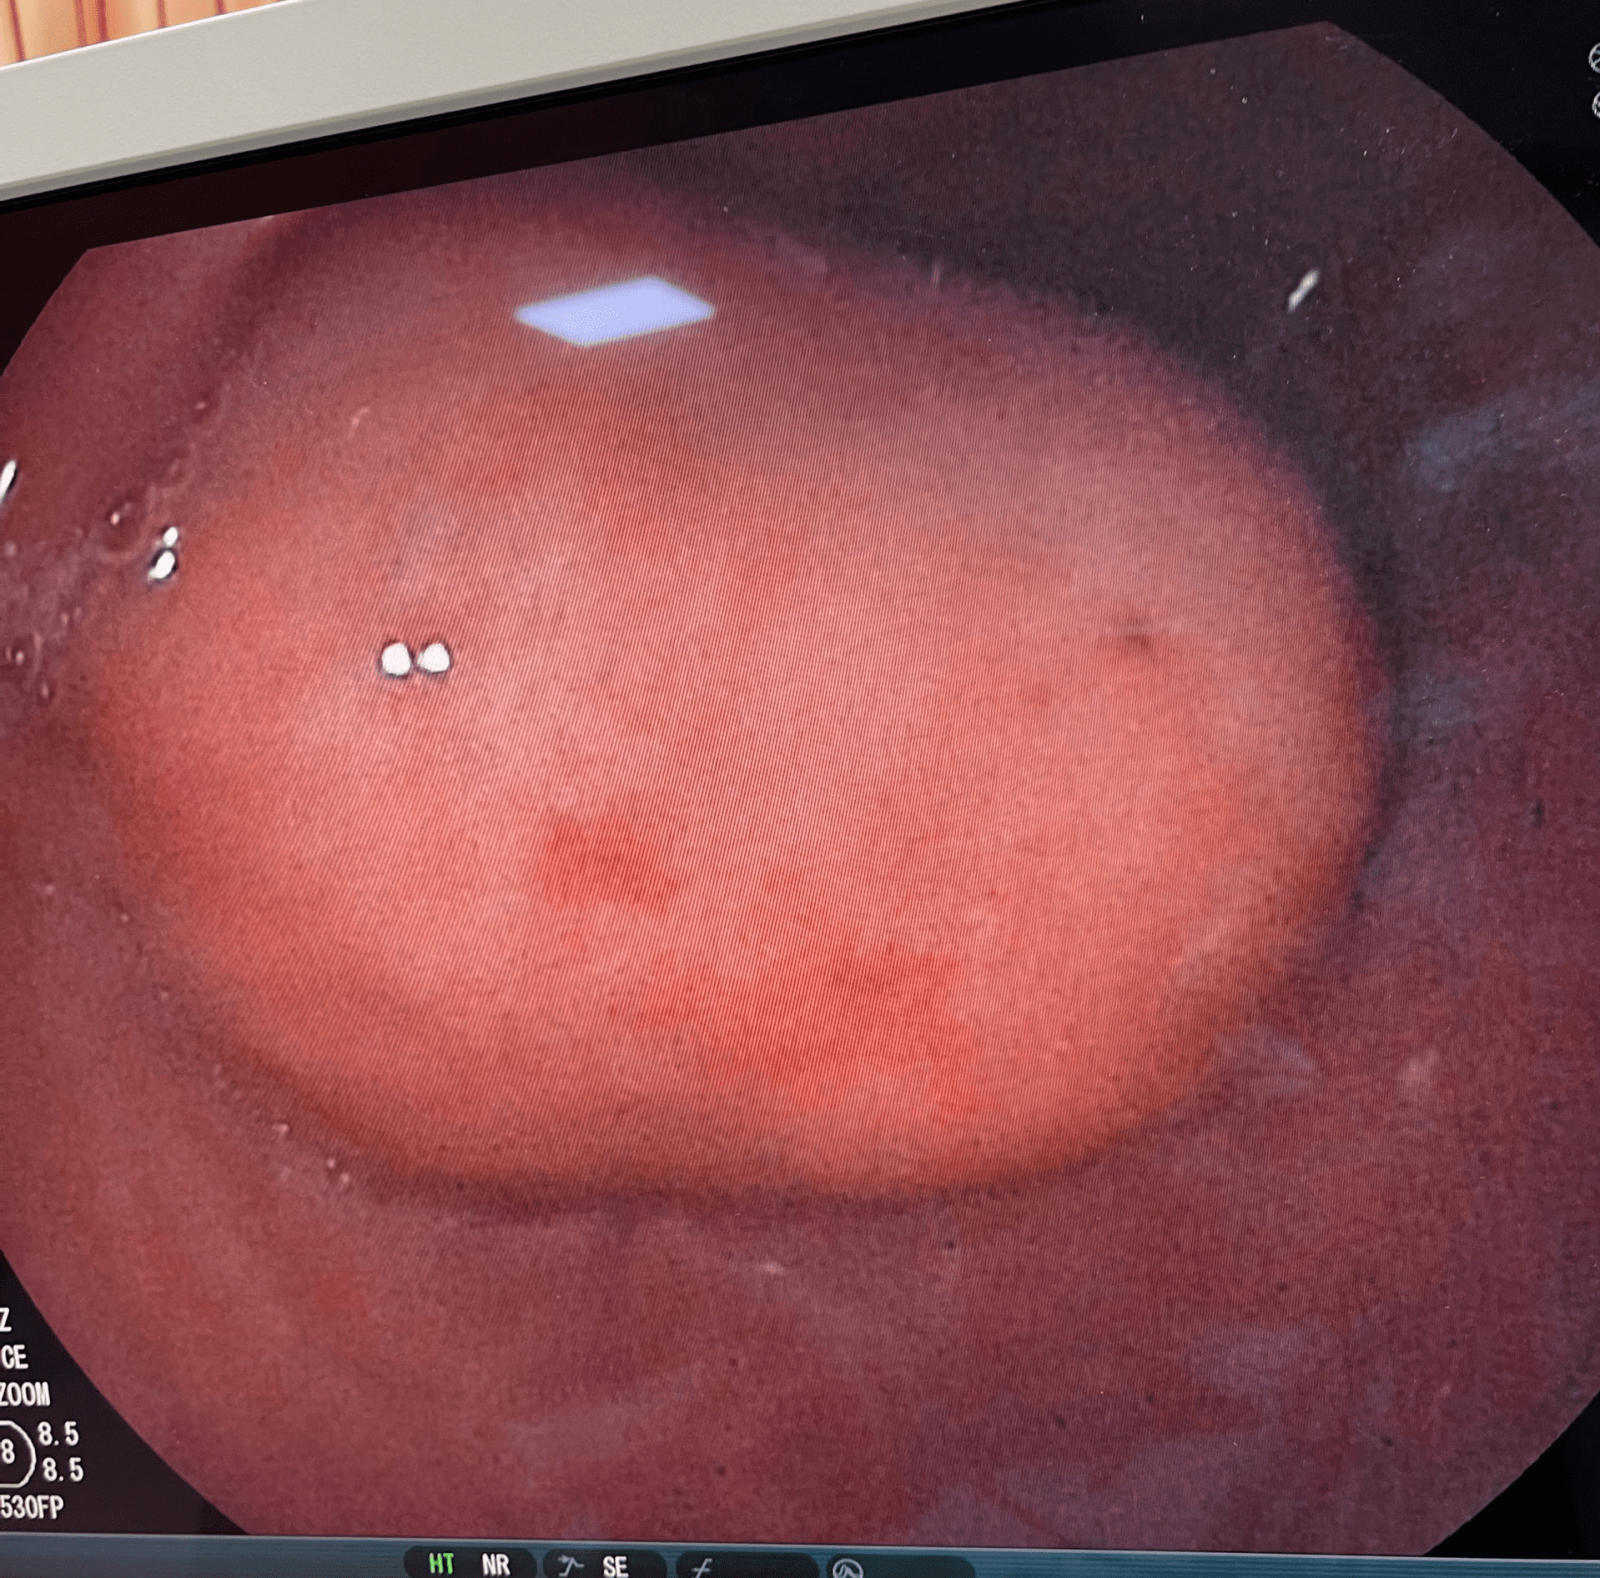

Bệnh nhân Tạ V.S (nam, 71 tuổi), có tiền sử hẹp mạch vành cách đây 8 năm, nhiễm Covid-19 cách đây 3 tháng, một tuần trước khi vào viện bệnh nhân xuất hiện đau bụng thượng vị, đầy hơi, đau tức ngực trái. Khám tại Trung tâm Y tế thành phố Móng Cái, qua kết quả nội soi, siêu âm và chụp cắt lớp vi tính ổ bụng của bệnh nhân phát hiện khối bất thường kích thước 6cm - 5.3cm trong dạ dày. Các bác sĩ đã hội chẩn và chẩn đoán U GIST dạ dày. Bệnh nhân được chỉ định phẫu thuật mổ cắt U GIST.

Khối U trong dạ dày qua hình ảnh nội soi